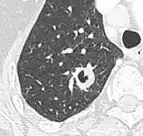

-

Part solid nodule.[9] -

Ground glass opacity nodule.[9]